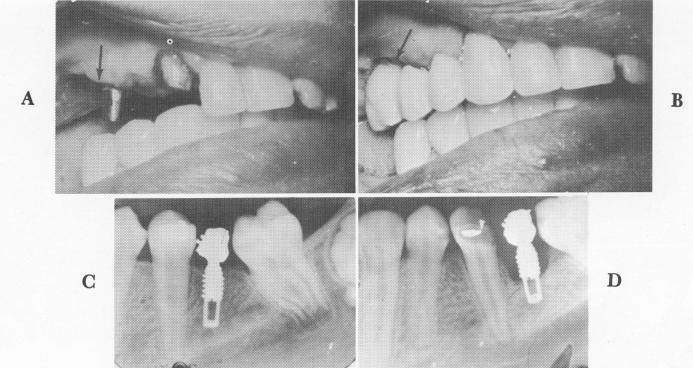

Fig. 14-33. A and B, Using a blade with an extra long neck is frequently preferable to cutting away a good portion of the tissue. Here the processed fixed partial denture had to be fitted to the atypical and irregular gum line because of the tissue removal. Arrows point to areas where the fibromucosal tissue was excessively removed, resulting in overlengthening of the molar crowns. C, Immediate postoperative x-ray shows bone around an unsupported single tooth implant. D, The bone damage is evident 12 months later around the unsupported vent-plant. Also, this was an earlier designed implant, which also contributed to its failure.

Single tooth implants unsupported by neighboring teeth will fail (Fig. 14-34). They must be immediately stabilized by a splint or the implant can move and prevent healing. No matter what type of implant is used, a temporary splint is needed unless a permanent one has been prepared beforehand.